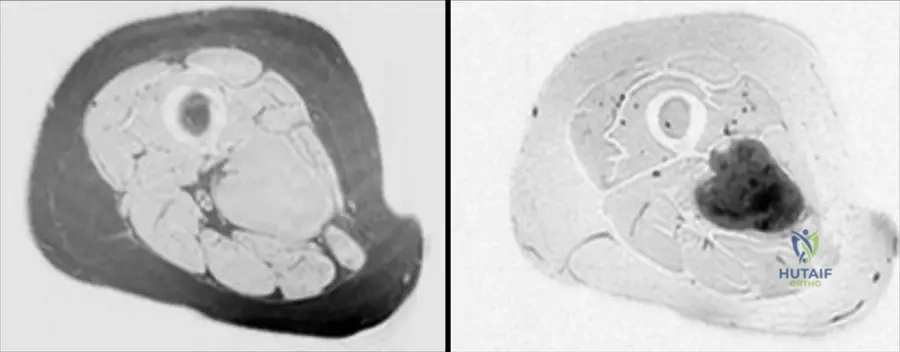

A 52-year-old male presents with a firm mass in his proximal forearm. An MRI is performed to evaluate the extent and characteristics of the lesion.

View Answer & Explanation

Correct Answer: A

Rationale: The clinical context for Fig. 9.15 states: "Axial T1(a) and T2-weighted image with gadolinium and fat saturation (b) showing a heterogeneous soft tissue sarcoma in the proximal forearm that is predominantly in the subcutaneous tissues abutting the adjacent myofascial plane." Main Distractor: B) Entirely within the deep muscular compartment. The image context explicitly states the lesion is "predominantly in the subcutaneous tissues," which contradicts a purely deep muscular location.

Question 10

A 60-year-old female presents with a growing mass in her proximal forearm. MRI images are obtained to characterize the lesion.

Rationale: The clinical context for Fig. 9.15 describes the lesion as a "heterogeneous soft tissue sarcoma." Heterogeneity is a common feature of sarcomas due to varying cellularity, necrosis, and hemorrhage. Main Distractor: B) Uniform signal intensity throughout the mass. This is incorrect, as the text explicitly describes the sarcoma in this image as "heterogeneous."